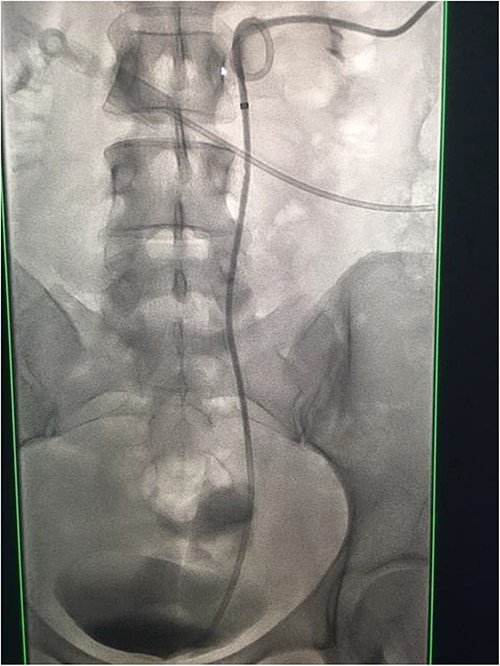

Under conscious sedation, using the previously inserted right percutaneous nephrostomy, antegrade access was achieved into the intrarenal collecting system and then into the proximal ureter. An 8 Fr × 11-cm access sheath was introduced. A guidewire was advanced antegradely through the site of ureteric transection and coiled in a position adjacent to the position of the guidewire that had been inserted retrogradely. A Gooseneck snare catheter was then passed over the guidewire and the snare was inserted (Figs 4 and 5). Under fluoroscopic guidance, the retrograde wire was retrieved and brought externally via the nephrostomy site, achieving through-and-through wire access (Figs 6 and 7).

Fluoroscopic images showing the retrograde wire successfully retrieved and brought externally via the nephrostomy site, achieving through-and-through wire access.